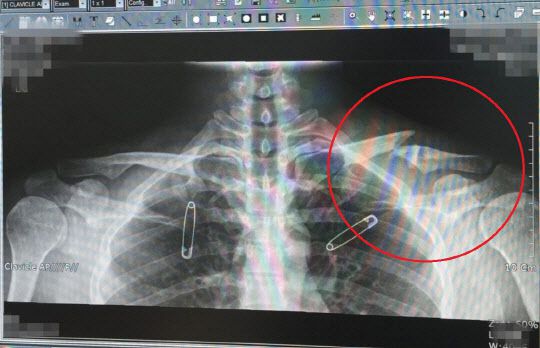

과거 유아인은 2013년 영화 촬영 중 어깨 근육 파열에 이어 2015년 골종양 판정을 받은 것으로 전해졌습니다. 당시 유아인은 병무청으로부터 '현역 자원 활용 불가' 판정을 받으며 면제가 되었습니다.

유아인이 골종양을 앓고 있다는 사실이 알려진 이후 참석한 드라마 제작발표회 현장에서 "오른쪽 어깨에 종양이 있지만 양성이다. 특이 케이스로 사이즈가 비이상 적으로 커져서 관찰을 유심히 하고 있다"고 설명했습니다.

당시 일부 매체들은 유아인이 골종양(골육종) 때문에 병역 면제 판정을 받았다고 보도했는데 일부 누리꾼들은 이에 대해 '골종양'과 '골육종'은 엄연히 다른 질병이라 지적하기도 했습니다.

유아인의 군면제 사유는 악성이 아닌 양성 골종양으로 양성 골종양은 종류도 많고 발생하는 부위도 다양합니다. 또 그 예후의 차이가 크기 때문에 완치를 장담할 수 없는 편으로 알려져 있습니다.